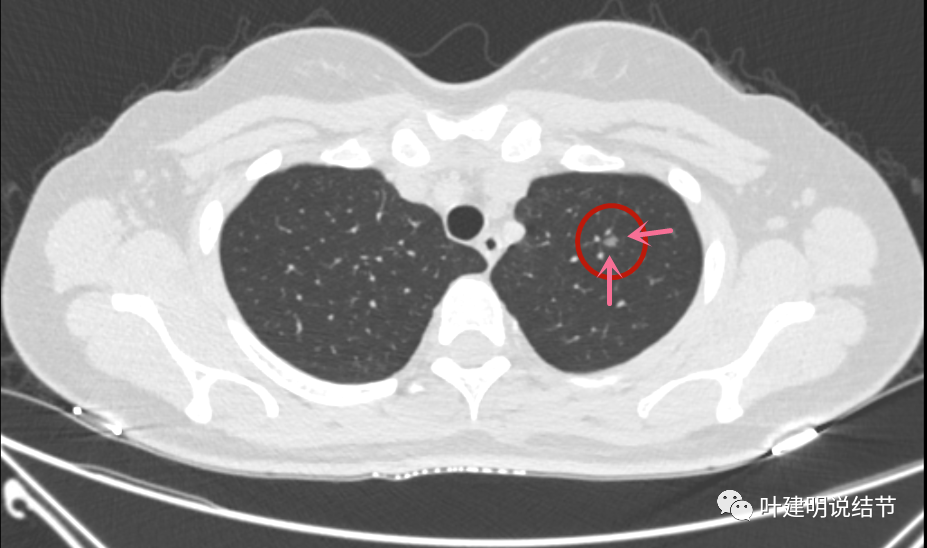

混合磨玻璃结节,伴有胸膜牵拉——肺腺癌